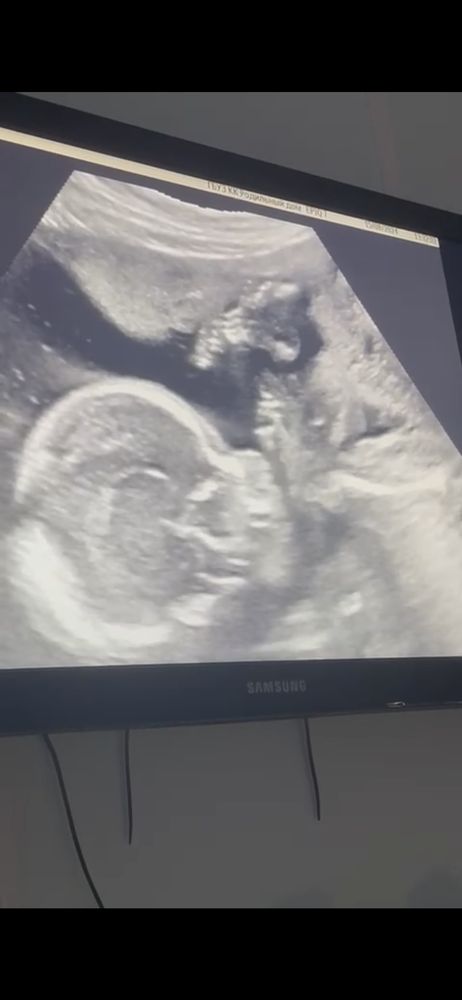

2 скрининг

Пол беременности уже за спиной. Совсем скоро мы встретимся ❤️ патологий на скрининге не выявлено, все анализы в норме, что не может не радовать.